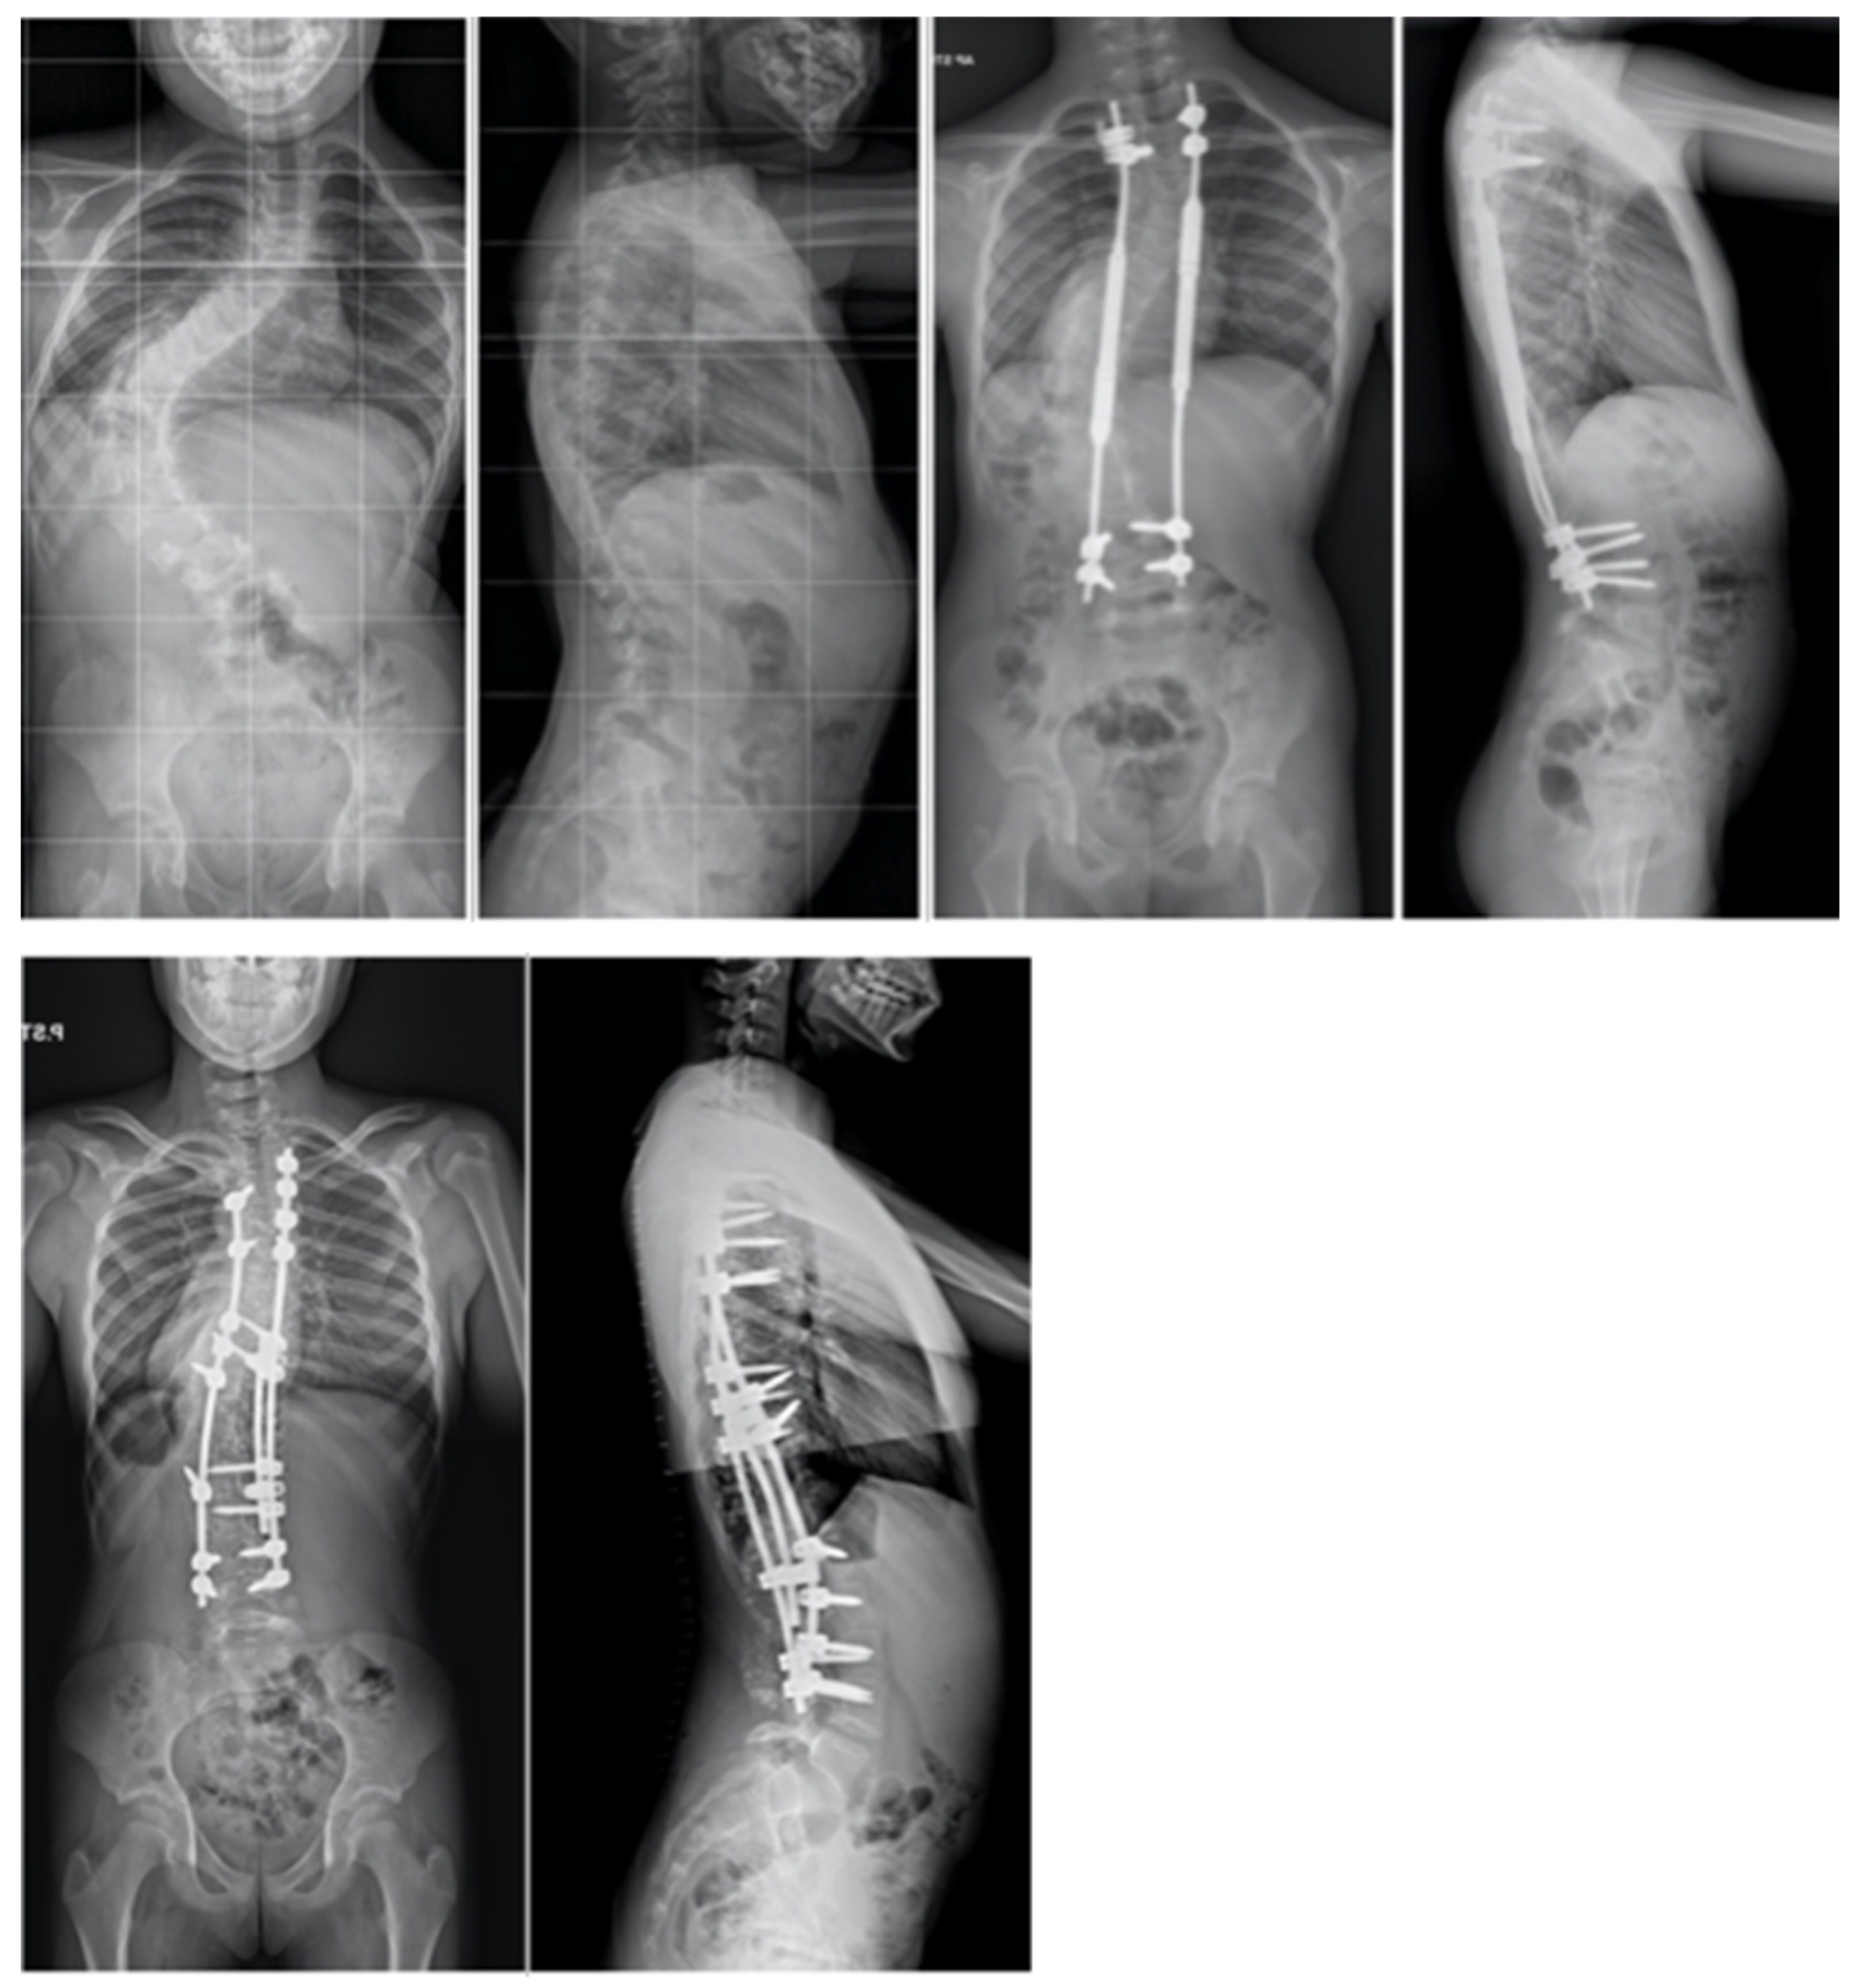

In the alternative approach delineated by Grabala et al. [44], patients were subjected to a two-phase surgical strategy. Initially, a comprehensive standard approach to the spine was carried out from the rear direction, enabling visualization of the spine at the specified stabilization levels. Facetectomy was performed at all spinal levels bilaterally, excluding the upper instrumented vertebrae (UIV). At all levels [73,74,75,76], a typical Ponte osteotomy was executed, with segmental screws being implanted at each level (at least on one side). A properly curved MCGR was positioned on the concave side of the curvature to achieve partial correction, while neuromonitoring guided the procedure. Pedicle screws on the convex side’s upper and lower levels were linked by a temporary short stabilizing rod, forming two firm blocks to strengthen the structure for future spinal distraction [44]. The patient was discharged after a five-day hospital stay, and weekly spinal distractions were performed over the next six weeks until reaching the maximum MCGR distraction point. Each distraction was carried out with maximum torque or until the observation of the “clunking phenomenon”. The forces applied during spinal distraction were of significant magnitude, and a single distraction control image was taken after six weeks of gradual lengthening of the magnetic rod. Subsequent to the completion of additional MCGR distractions, a final correction of the spinal deformity was conducted, involving the removal of the MCGR. The ultimate correction encompassed a blend of rod distraction/compression, apical translation, and segmental derotation. In the ensuing treatment phase, the resultant distraction length of the rod was measured using a ruler [44]. Figure 11 shows the treatment of a 16-year-old female diagnosed with severe adolescent idiopathic scoliosis with staged surgery, involving a temporary internal distraction device with MCGR for initial intervention, followed by PSF.

Figure 11.

During the observation period, pre- and post-operative radiographs were utilized to monitor the treatment progress of a 16-year-old female diagnosed with severe adolescent idiopathic scoliosis. Staged surgery was conducted, involving a temporary internal distraction device with MCGR for initial intervention, followed by the implementation of double Co-chr 6.0 rods for final correction of the spinal curvature.

The study conducted by the authors of reference [44] concluded that the utilization of a magnetically controlled growing rod (MCGR) as a temporary internal distraction device for neglected scoliosis in adolescent patients does not present any significant advantages. However, it was found that surgery for severe scoliosis can be performed safely with lower risks of complications by implementing pre-operative HGT. An important intraoperative challenge associated with utilizing an MCGR as a temporary internal distraction device was the occurrence of a 50% probability of temporary neuromonitoring changes due to excessive force on the spine and substantial distraction. Nonetheless, both techniques yielded comparable clinical, radiographic, and pulmonary function outcomes. The use of HGT was shown to result in reduced blood loss and shorter anesthesia duration. The strategy of achieving partial correction was highlighted as crucial in preparing for subsequent interventions by gradually decreasing the curvature, thereby decreasing the surgical complexity and the likelihood of neurological complications as described in reference [34]. Another study by Koller et al. examined a similar method of temporary internal distraction utilizing MCGR for the management of severe scoliosis [81]. A group of seven patients with a primary curvature exceeding 100° underwent treatment involving temporary MCGR placement. The treatment protocol included posterior instrumentation, periapical release with advanced Ponte osteotomies, segmental pedicle screw insertion, and the use of a single MCGR. Subsequent to about 14 days, a second surgical procedure was carried out to remove the MCGR, achieve final correction, and perform fusion. Notably, none of the patients encountered major complications or neurological deficits. The staged surgical approach led to an average correction of the post-operative primary curve to 39° (67%). The ultimate conclusions of the study propose that this technique may have the ability to decrease the necessity for HGT and the high-risk 3 Column Osteotomies (3CO) in the correction of severe scoliosis as outlined in reference [81].